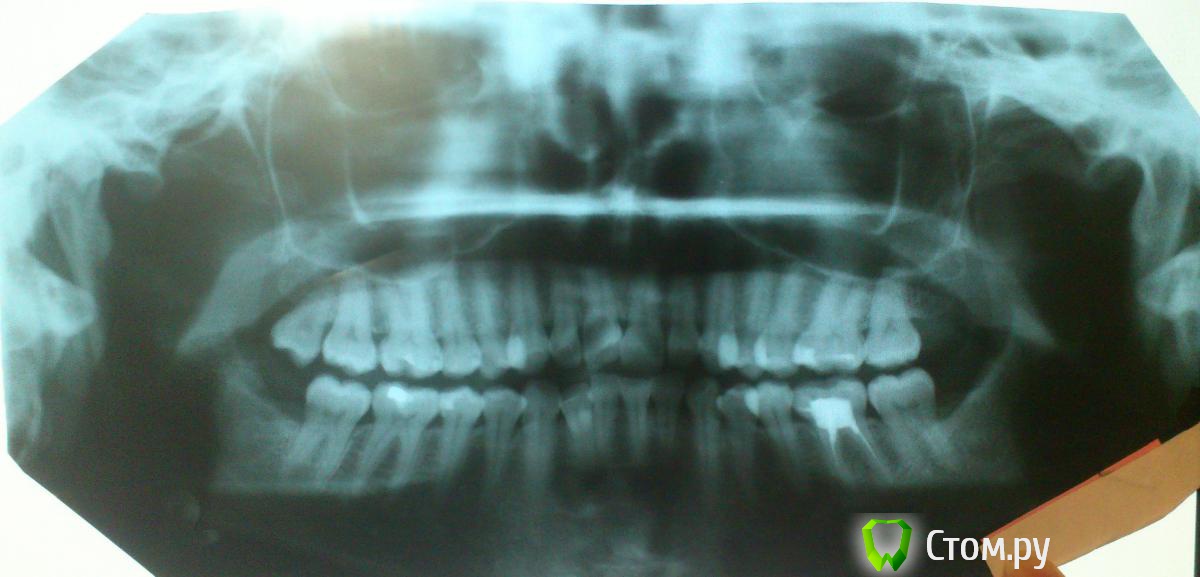

arTika Опубликовано 2 июля, 2014 Поделиться Опубликовано 2 июля, 2014 Здравствуйте, уважаемые доктора!!!Уже несколько лет щелкает сустав при открывании рта, челюсть двигается вниз с-образно. К этой проблеме добавился шум в ушах, иногда боли в области виска, бывает так, что открывая рот не могу завершить движение, как бы заклинивает челюсть. Зубы раньше стояли ровно, постепенно стали наклонятся в разные стороны. Щелчки в суставах стали беспокоить уже после, появления скученности. Хочу начать лечение, была на консультации у ортодонта. Врач сказал, что зубы выровнять мне может, но сустав во время лечения может еще сильнее болеть, в итоге ортодонт обещает, что результатом будут только ровные зубы, с внчс ситуация не изменится. Но я не с эстетической стороны хочу начать лечения, меня больше беспокоит ситуация с суставом, так как очень быстро ситуация ухудшается. Была на консультации у ортопеда, мне рекомендовали удалить все 8-рки, сделали слепки. 8-рки мне удалили. Сейчас ортопед назначил трг и дальше брекет лечение( при этом возможно необходимо удалить все 4 на н/ч и на в/ч) у ортодонта, а после брекетов уже приходить к ортопеду. Снимок сустава никто не назначал. На форуме читаю, что тем у кого проблемы с суставом сначала изготавливают капы и если нужно потом брекеты. Поэтому я переживаю, что если сейчас мне просто приклеят брекеты, зубы станут ровными, а суставам станет только хуже и я вообще не смогу открывать рот или мне прийдется искать у кого перелечиваться, а это еще сложнее, ведь врачи этого ох, как не любят. Скученность сильная, но раньше зубы стояли ровно до появления 8-рок, значит им места хватало, тогда зачем сейчас удалять здоровые 4-рки?В связи с этим у меня возникли вопросы:1. С чего начинать лечение? С брекетов или индивидуальной капы?2. Если с капы, то какая нужна?3. Нужно ли удалять 4-рки? Если удалять, то как это повлияет на внешность в моем случае, ведь челюсть и так узкая?4. Нужно ли до лечения делать снимки самого сустава? Если да, то какие?5. Можно ли вообще добиться выздоровления сустава в моем случае?Я понимаю, что заочно сложно давать консультацию, но врачи в нашем городе такое впечатление, что сторонятся пациентов с нарушениями внчс, меня отсылают от одного врача к другому, как будто никто не хочет брать на себя ответственность (или не может) и лечение не начинается, Помогите мне пожалуйста!!!! Порекомендуйте врача, который сможет помочь и вылечить меня!Если нужно могу выложить фото слепков, которые мне сделали. Заранее спасибо всем! Ссылка на комментарий